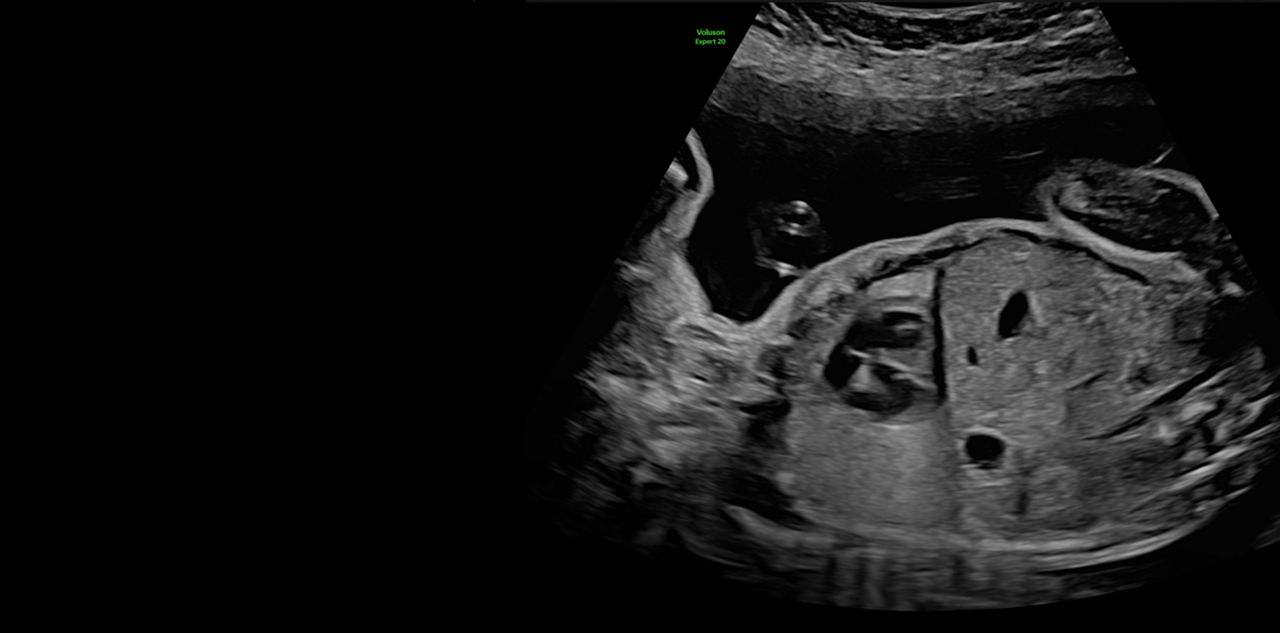

Refine Clinical Insights

Extraordinary clarity and definition so you can focus on early detection and intervention.